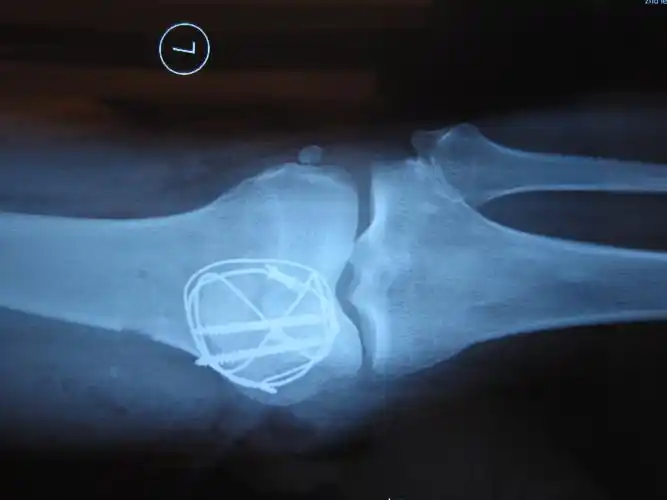

术前x光片

髌骨横型骨折,术前术后影像对比

征集髌骨骨折x光片按要求提供给予积分